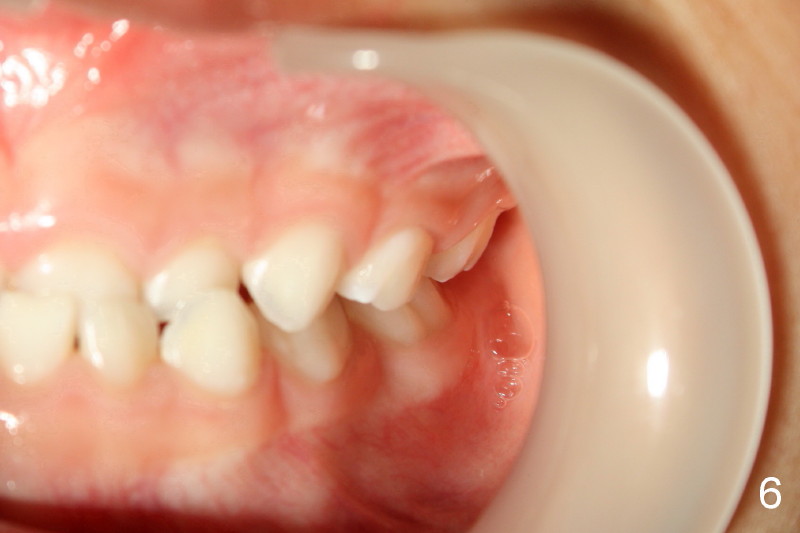

Right canine occlusion is Class I (Fig.3), whereas left Class III (Fig.4).